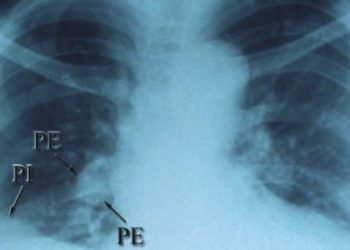

![Fibrinolysis for pulmonary embolism may prevent hemodynamic collapse [PEITHO trial]](https://www.2minutemedicine.com/wp-content/uploads/2014/04/762px-SaddlePE-350x250.png)